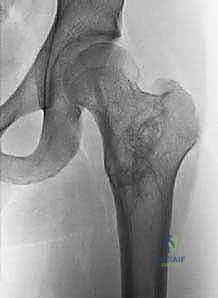

تُظهر هذه الأشعة السينية (X-ray) كيس عظم أحادي الغرفة (UBC) في الجزء العلوي من عظم العضد. لاحظ كيف أن الكيس يسبب ترققاً في قشرة العظم دون أن يخترقها.

- الأشعة السينية (X-rays):

- هي الخطوة الأولى والأساسية.

- في الـ UBC، تظهر الآفة كمنطقة شفافة (سوداء) مركزية داخل العظم. وهناك علامة مميزة تُسمى "علامة الورقة المتساقطة" (Fallen Leaf Sign)، حيث تسقط قطعة صغيرة من قشرة العظم المكسورة داخل الكيس المملوء بالسائل، وهي علامة مؤكدة بنسبة 100% تقريباً على الـ UBC.